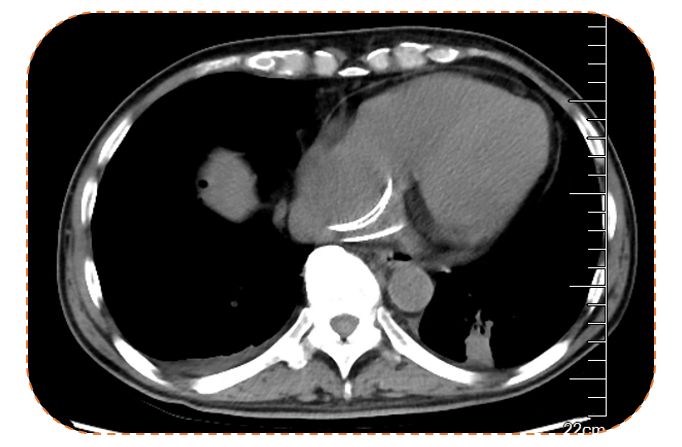

影像学检查:可见肝周少量积液,无其他明显异常